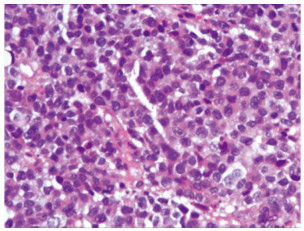

入院后进行相关的实验室检查,血常规提示血红蛋白为82 g/L。肝功能、肾功能、电解质、凝血相关指标、CEA、CA19-9、细胞角蛋白正常。下腹部CT扫描显示膀胱后壁弥漫性增厚,周围组织边界不清,见图 1。CT扫描还显示左侧输尿管积液,左侧肾盂扩张和左侧肾周积液,未发现明显的淋巴结肿大或远处转移。膀胱镜活检病理提示:(膀胱)高级别浸润性浆细胞样尿路上皮癌,HE染色见图 2。免疫组织化学:CK(+),P40(+),P63(+),CK高(+),CK7(+),CK8/18(+),CK20(+),CD138(+),CD38(-),CD56(-),CK5/6(-),EMA(-),Desmin(-),Vimentin(-),Syn(-),CgA(-),LCA(-),MUM-1(-),Ki-67(+,约80%)。